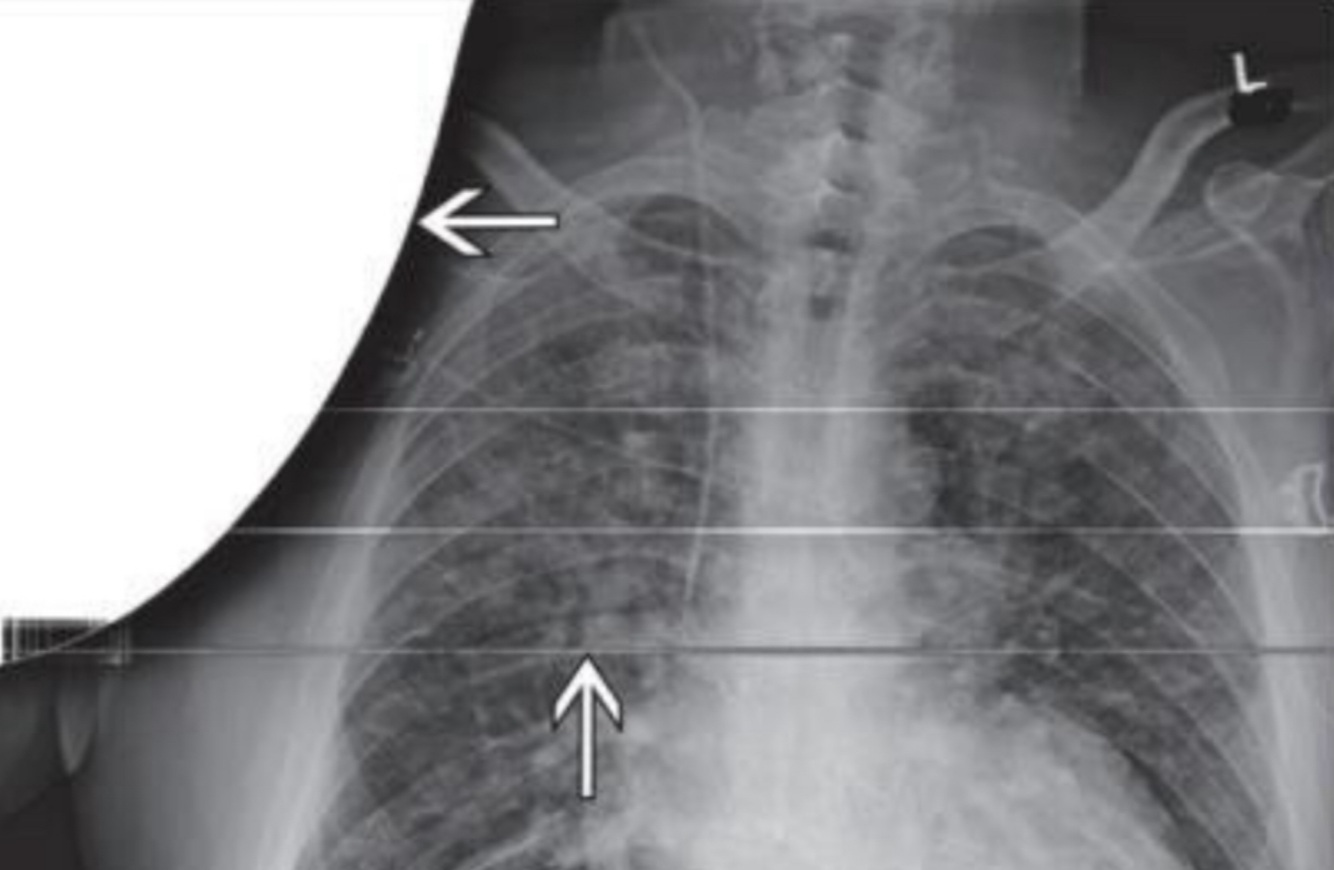

Foreign body: Surgical Sponge